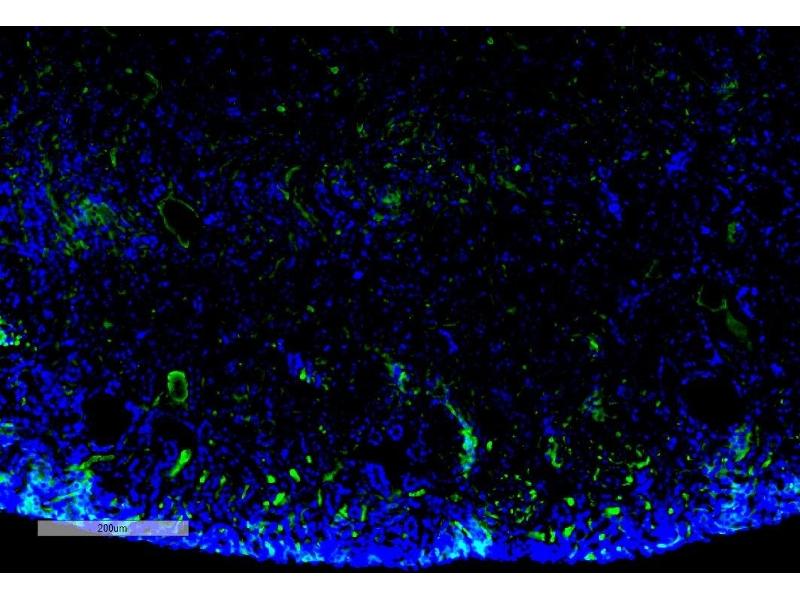

The PE-conjugated 小鼠 单克隆 anti-Malondialdehyde antibody (Clone 11E3) (ABIN5067377) specifically detects Malondialdehyde in ELISA, WB, ICC, IF 和 IHC.

ELISA, Western Blotting (WB), Immunocytochemistry (ICC), Immunofluorescence (IF), Immunohistochemistry (IHC)